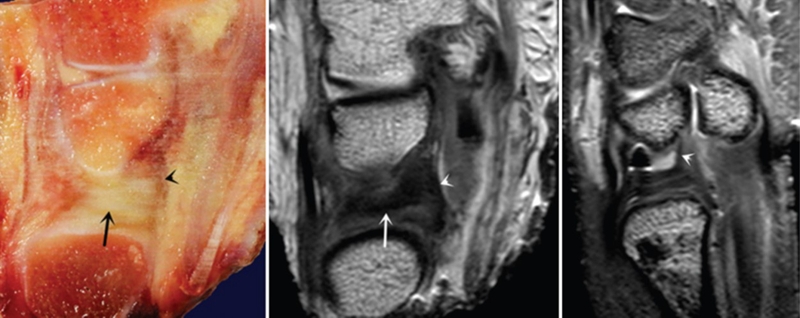

ⅠA,TFCC中心穿孔,A、B三角软骨盘正常弓形低信号缺损;C轴位显示三角软骨盘中心的高信号区与D关节镜一致

ⅠB,TFCC尺侧撕裂;TFC尺侧附着处信号增高

ⅠC,尺三角韧带撕裂

ⅠD,TFC桡侧撕裂,桡侧附着处及桡尺关节处信号增高

ⅡA,TFC局部变薄,但结构完整

ⅡB,TFC局部变薄,但结构完整,月骨软骨厚薄不均

ⅡC,TFC中心撕裂,月骨软化,月三角韧带完整

ⅡD,TFC中心撕裂,月骨软化,月三角韧带缺如

图30 ⅡE,TFC中心撕裂,月骨、尺骨软骨软化,月三角韧带缺如,桡尺关节骨质增生